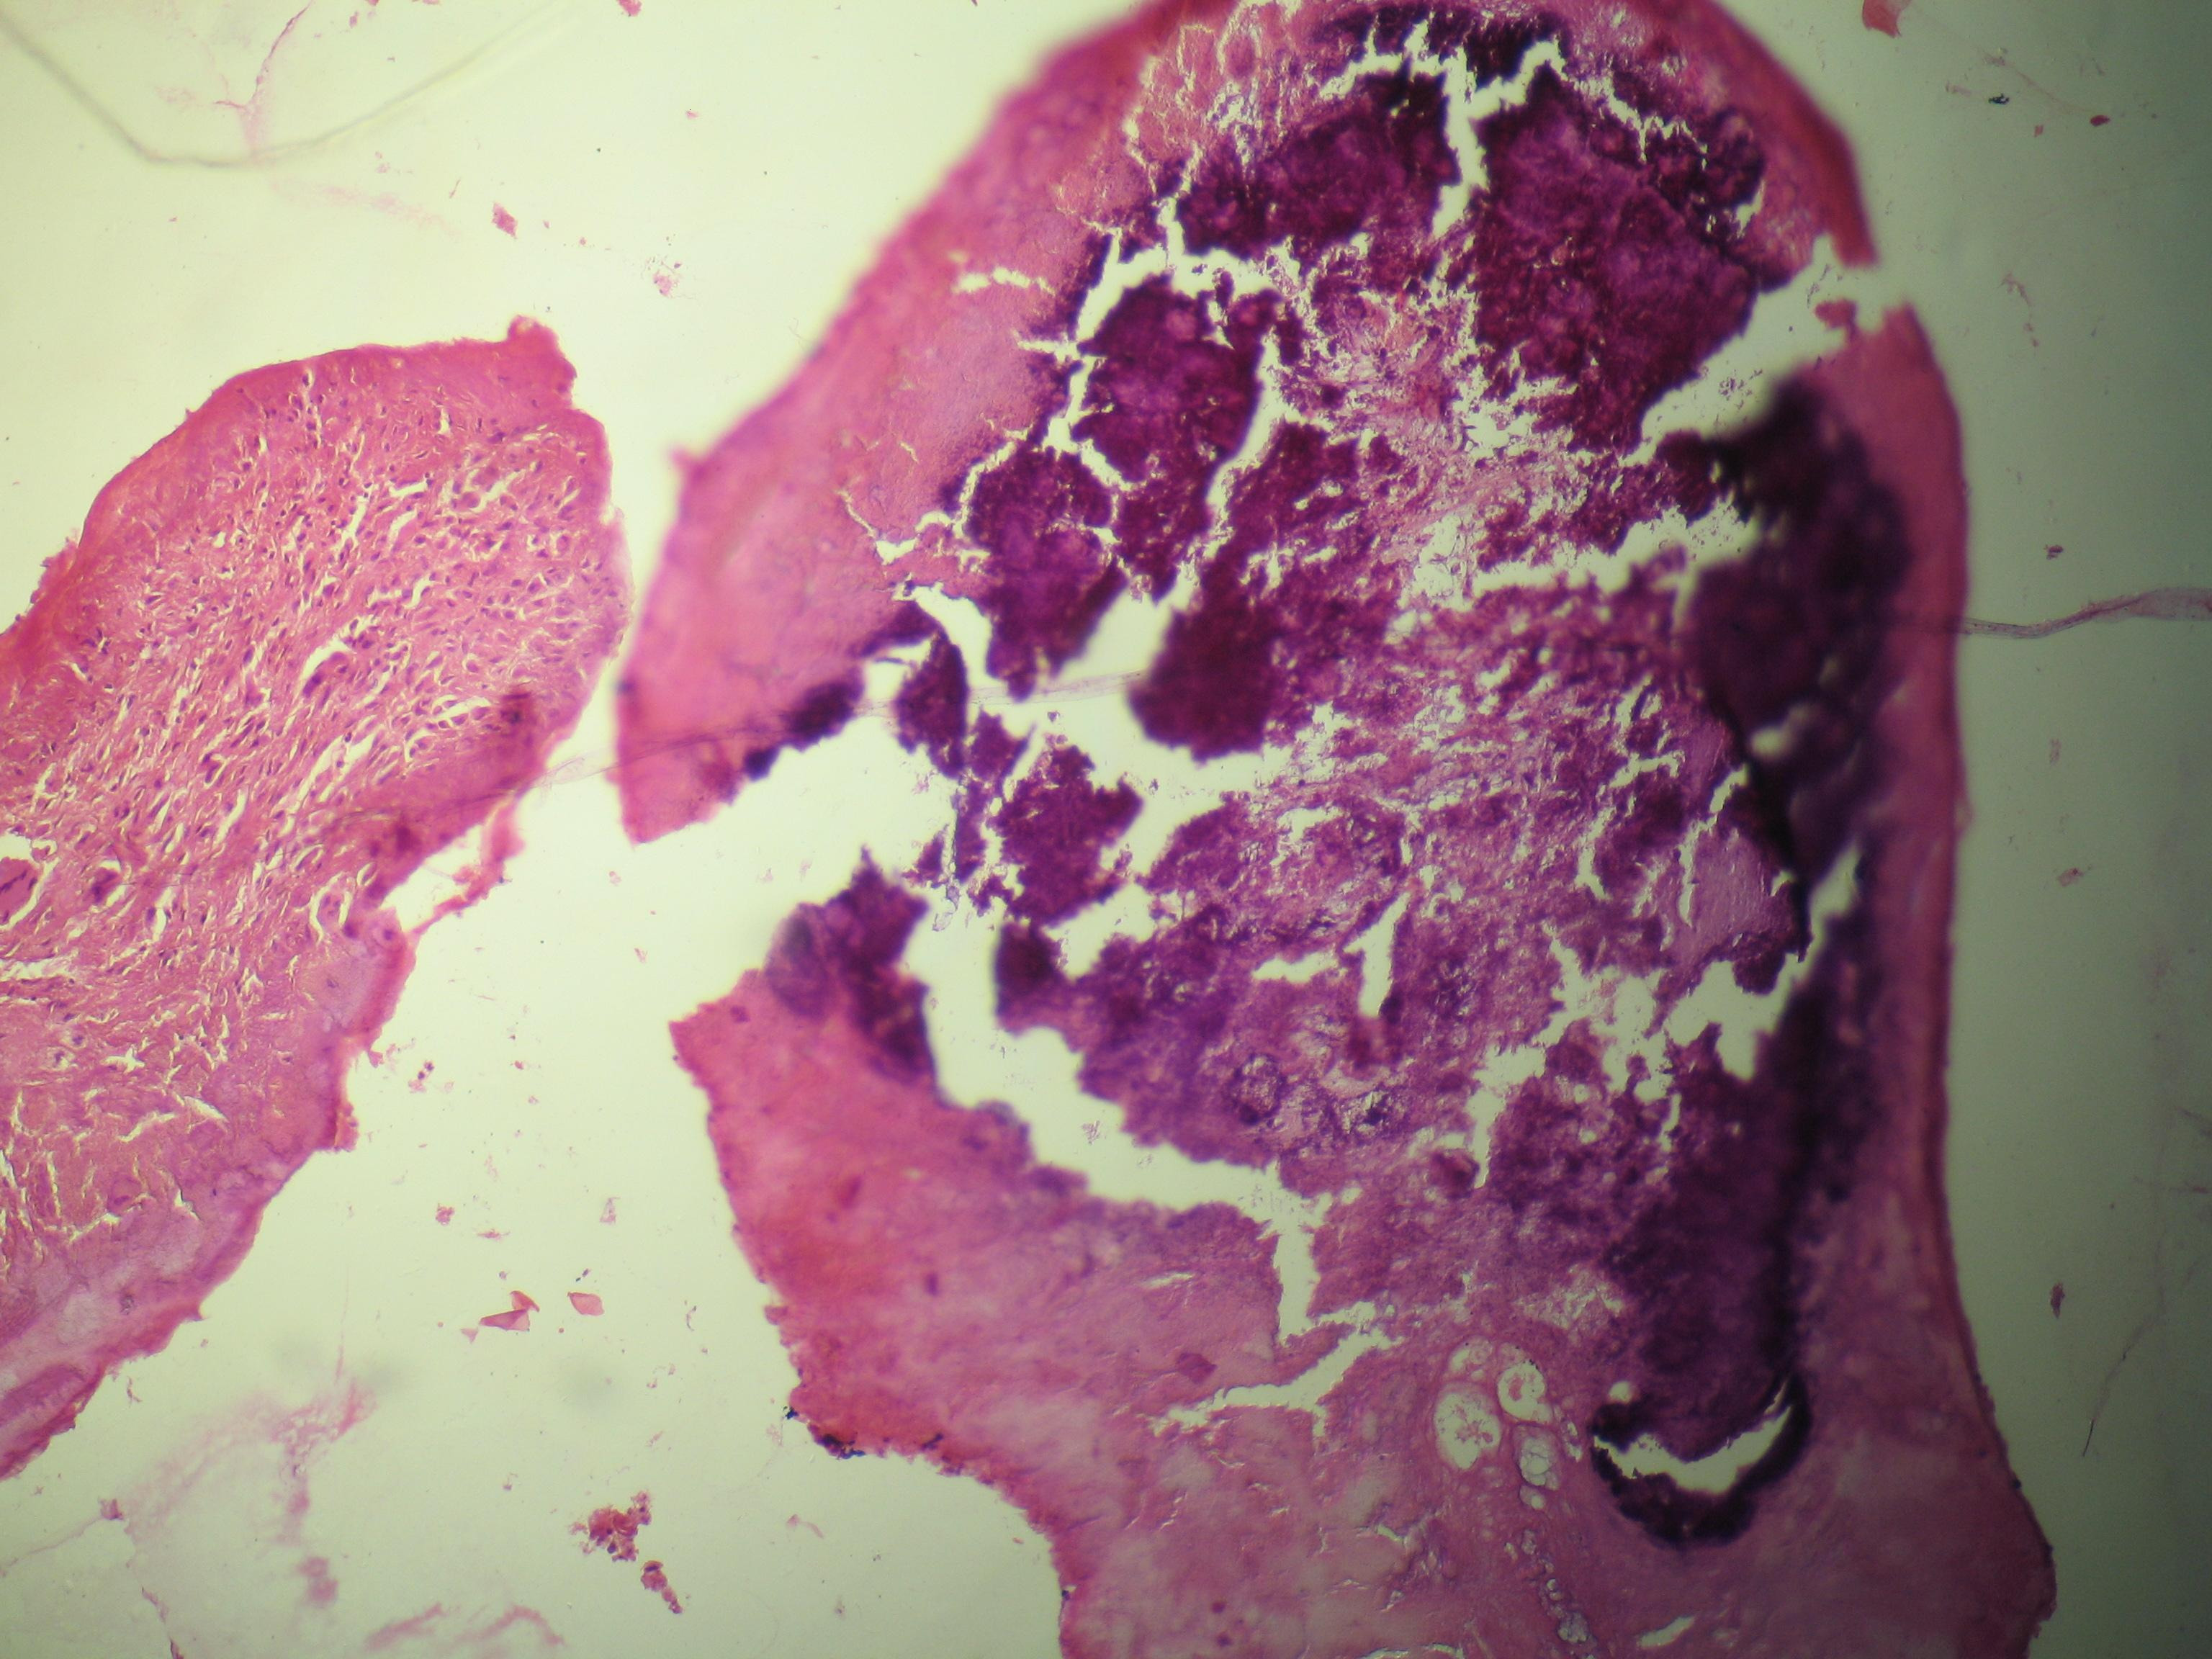

Данный тип дисфункции сердечной мышцы всегда имеет наследственный характер. При аритмогенной кардиомиопатии часть здоровых тканей заменяется соединительной или жировой тканью. Этот вид кардиомиопатии чаще всего передается по наследству, хотя в редких случаях может быть и приобретенным. Например, болезнь Наксоса относится к заболеваниям, которые передаются по рецессивному типу. На сегодняшний день аритмогенная кардиомиопатия изучена недостаточно, поэтому полное понимание ее этиологии остается затруднительным.

Рестриктивная кардиомиопатия — это самый редкий вид нарушений в развитии миокарда. Специалист может диагностировать данный тип патологии по диастолической дисфункции левого желудочка, реже — правого. В категорию «рестриктивная кардиомиопатия» входят несколько заболеваний, которые характеризуются типичными изменениями в миокарде. Эти состояния могут быть вызваны:

- гемохроматозом;

- карциноидными опухолями;

- интоксикацией антрациклинами;

- амилоидозом;

- эозинофилией;

- склеродермией;

- саркоидозом.